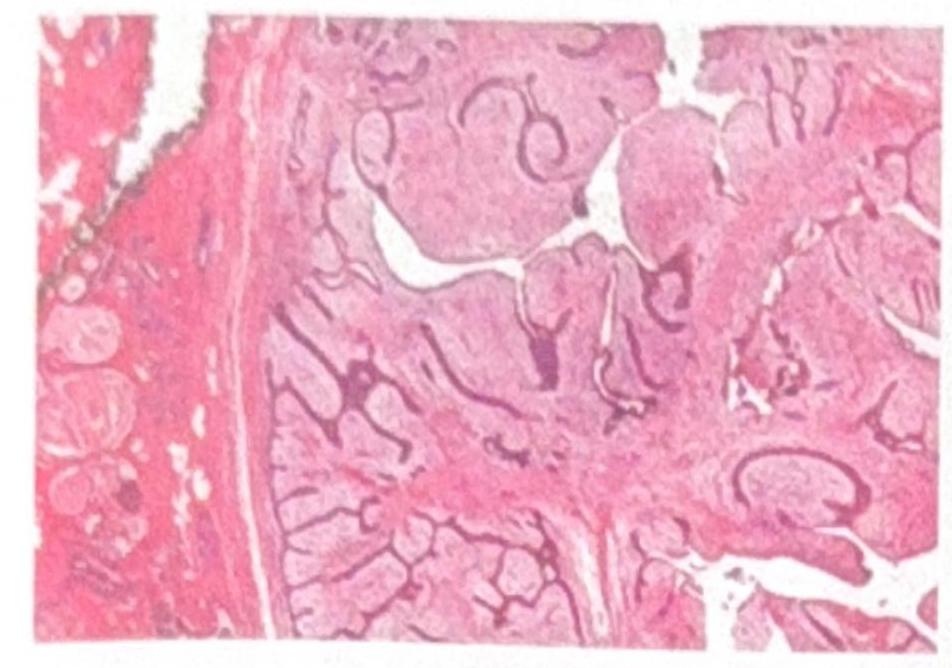

A 40-year-old female presents with an irregular 5 × 6 cm mass in the right breast. Histopathological examination reveals the image shown. What is the most likely diagnosis?

Explanation: ***Phyllodes tumor*** - The image demonstrates a characteristic **leaf-like or cleft-like stromal growth pattern** often seen in phyllodes tumors [1]. The stroma is cellular and appears to project into ductal spaces, leading to the formation of slit-like spaces [1]. - Phyllodes tumors are typically **large (5 cm or more)**, firm, and solitary, with a rapid growth rate, consistent with the described 5×6 cm mass [1]. - They show a **biphasic pattern** with both epithelial and stromal components, where the stromal component predominates [1]. *Fibroadenoma* - While fibroadenomas are biphasic like phyllodes tumors, they usually present with a more uniform, less cellular stroma and less pronounced epithelial-stromal clefting [1]. - Fibroadenomas also do not typically grow as large as 5-6 cm with such aggressive stromal patterns in a 40-year-old. - The stroma in fibroadenoma is less cellular and lacks the leaf-like architecture [1]. *Invasive ductal carcinoma* - Invasive ductal carcinoma would show **infiltrating cords, nests, or tubules of malignant epithelial cells** invading through the stroma with associated desmoplasia [2]. - The biphasic leaf-like architecture with stromal fronds protruding into epithelial-lined spaces is not characteristic of carcinoma. - While it can present as a large irregular mass, the histological pattern is distinctly different from the image shown [2]. *Intraductal papilloma* - Intraductal papilloma presents with **arborizing fibrovascular cores lined by epithelial cells** within dilated ducts, typically near the nipple. - They are usually small (a few millimeters to 2-3 cm) and do not typically present as large 5-6 cm masses. - The prominent stromal overgrowth with leaf-like pattern seen in the image is not characteristic of papilloma. **References:** [1] Kumar V, Abbas AK, et al.. Robbins and Cotran Pathologic Basis of Disease. 9th ed. The Breast, pp. 1072-1074. [2] Kumar V, Abbas AK, et al.. Robbins and Cotran Pathologic Basis of Disease. 9th ed. The Breast, pp. 1066-1068.